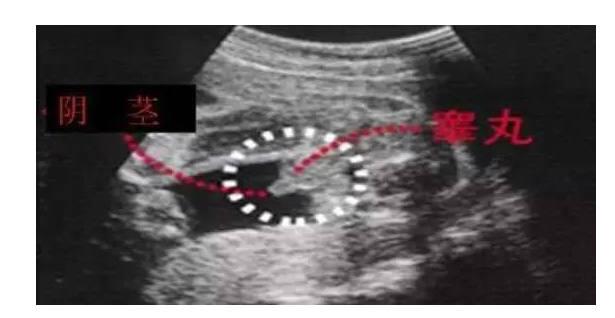

看到红圈里小小的东西了吗?不容易被发现,如果没有人指出,可能准妈妈不一定知道是什么的,但一说出来,就知道了。

"凸出的东西" 是他的标记: 你们看到圆圆的是蛋蛋,如果看到圆圆的加小肠的就是全部丁丁。

看到胎儿宝宝的小丁丁了吗?虽然现在已经不重男轻女了,但是所有准妈妈都会好奇肚里的宝贝是男宝还是女宝,无论如何,宝宝健康才是最重要的,祝好孕!